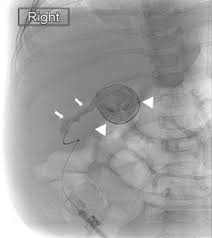

Hepatocellular cholestasis results from impairment of bile formation and indicates defective functioning of most or all hepatocytes. Biliary atresia imaging accessed 26 october 2017) fetal / embryonic form: Unequivocal evidence of intestinal excretion of radiolabel confirms patency of the extrahepatic biliary system. Congenital absence of biliary tree us: Biliary atresia is a serious liver disorder that occurs before or shortly after birth when a baby's bile ducts (the tubes that carry bile from the liver) become blocked. Gallbladder length less than 19 mm is suggestive for atretic gallbladder 2. Purpose to evaluate the incremental value of a combination of magnetic resonance cholangiopancreatography (mrcp) and ultrasonography (us), compared to us alone, for diagnosing biliary atresia (ba) in neonates and young infants with cholestasis. It is the most common cause of.

This case presents the classic sonographic findings of biliary atresia, including: It is the most common cause of. Imaging features on preoperative ultrasonography (us) and magnetic resonance imaging (mri) were compared between the cba and cc. Ba is not associated with calculi, neoplasm, or rupture. Biliary atresia is a rare condition in newborn infants in which the common bile duct between the liver and the small intestine is blocked or absent.

Materials and methods the institutional review board approved this retrospective study. Gallbladder length less than 19 mm is suggestive for atretic gallbladder 2. However, we noticed a few discrepancies that can leave the readers baffled. Über 7 millionen englischsprachige bücher. The us and mrcp studies were both performed on 64 neonates and. Based on the results of our series, the size of the gallbladder does not seem to be a decisive finding for the diagnosis of biliary atresia. It presents with jaundice during the early weeks of life, with an incidence of 0.5 to 0.75 cases Imaging in biliary atresia tuesday, october 26, 2004 biliary atresia a condition in which there is aplasia or obliteration of some or all of the extrahepatic biliary tree: